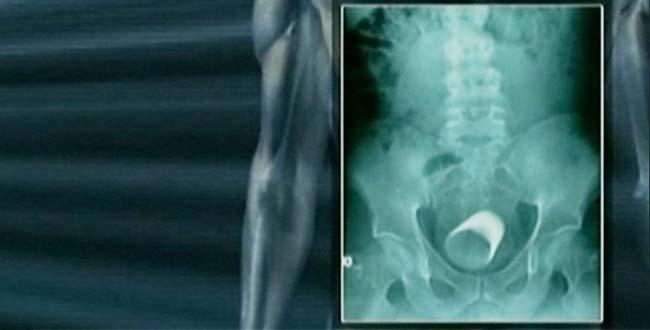

Marib, Yemen is a haven for radical Islamics, says one of SOFREP’s DIA sources. “It’s also likely home to the new surgeon Al Qaeda has recruited to continue its quest to implant explosives into the bellies of women and children.”

Now add innocent children to the recipe of hate by surgically implanting bombs in their bellies and you’ve gone too far in my book.